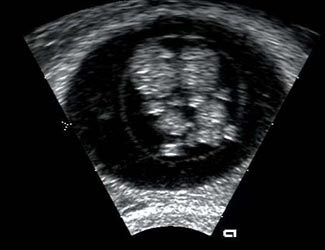

Αθήνα: Η έγκαιρη διάγνωση και η άμεση έναρξη της θεραπευτικής αγωγής μπορούν να βελτιώσουν την ποιότητα ζωής των ασθενών που πάσχουν από συγγενή καρδιοπάθεια, βοηθώντας τους παράλληλα να ζήσουν περισσότερο.